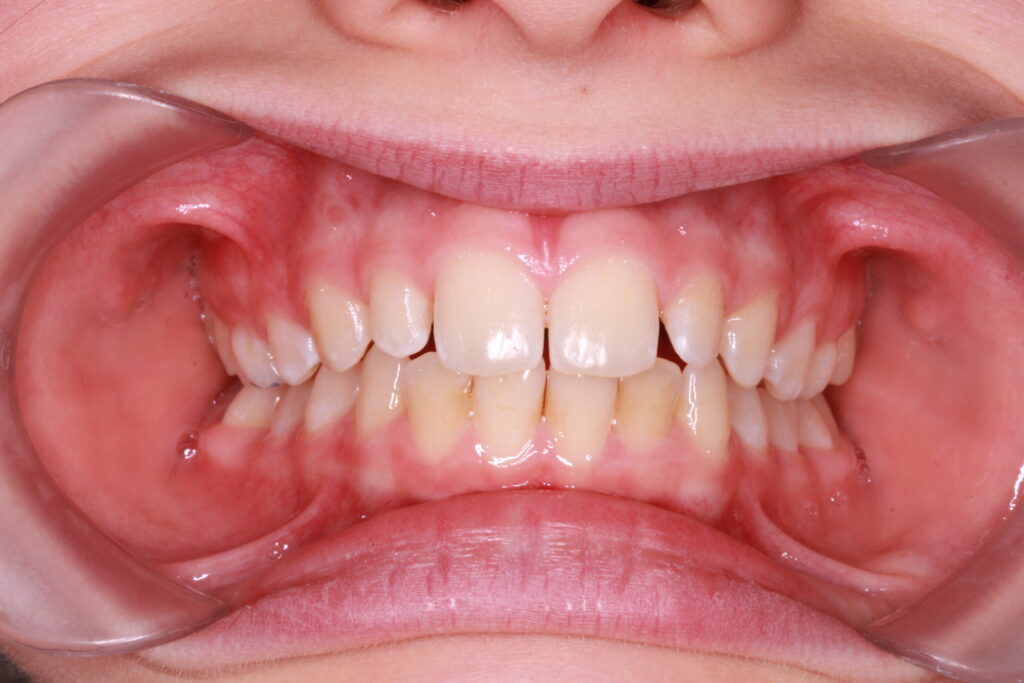

Az ALF készülék nem az agresszív erőhatásokra, hanem a funkcionális erők finom, biológiailag kíméletes irányítására épít. A klinikai tapasztalatok szerint ez tökéletes elég és mind a fogív fejlesztésében, keresztharapások megszűntetésében, helyteremtésben mind a nyelvtér növelésében jól működik.

A leggyakoribb a vegyes fogazat időszakában (6–11 év), de alkalmazható teljes tejfogazatban is nagyon korai kezelések esetében, akár 3-4 éves kortól is.